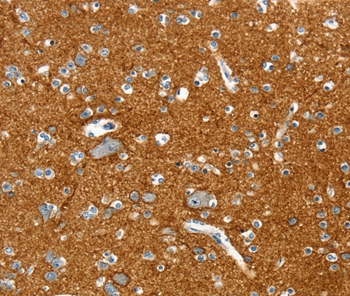

Immunohistochemical analysis of paraffin-embedded Human brain tissue using #36708 at dilution 1/20.